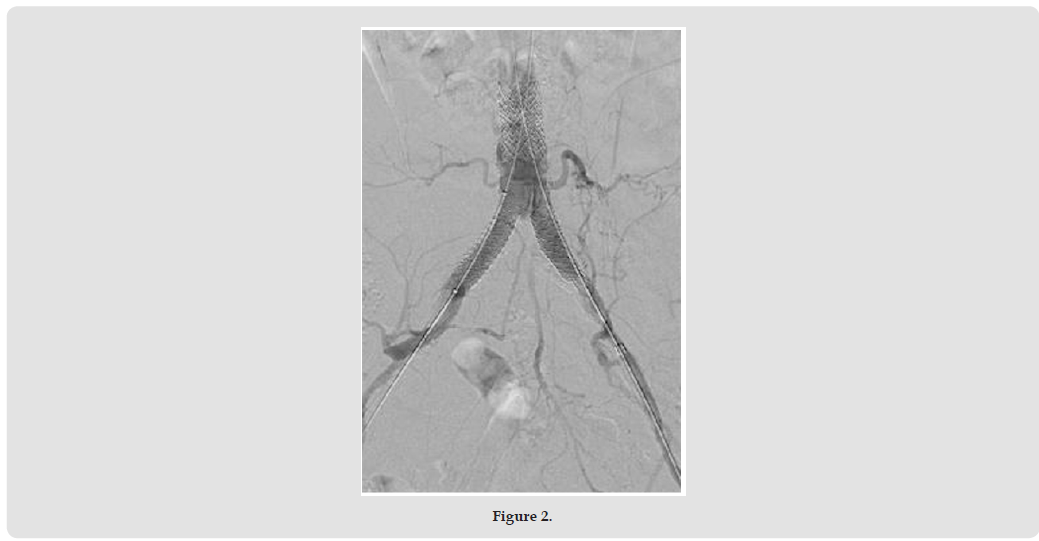

On the right side, the 18x38 mm BeGraft® Aortic Stent Graft (Bentley) was positioned halfway between the inferior mesenteric artery and the bifurcation, as planned (Figures 2 & 3). From both sides, a 10x37 mm BeGraft® Peripheral Stent Graft (Bentley) was deployed without predilatation into the iliac artery, positioned 10 mm up the aorta. After opening with a simultaneous kissing technique, angiography showed good results (Figure 4) and then the left side was stented with an 8x37 mm BeGraft® Peripheral Stent Graft (Bentley) with 10 mm overlap. The overlap was re-expanded with the 10 mm BeGraft® peripheral balloon. On control angiography, the inferior mesenteric artery and both internal iliac arteries remained open (the left side was also patent despite the preliminary CTA image) (Figure 5).